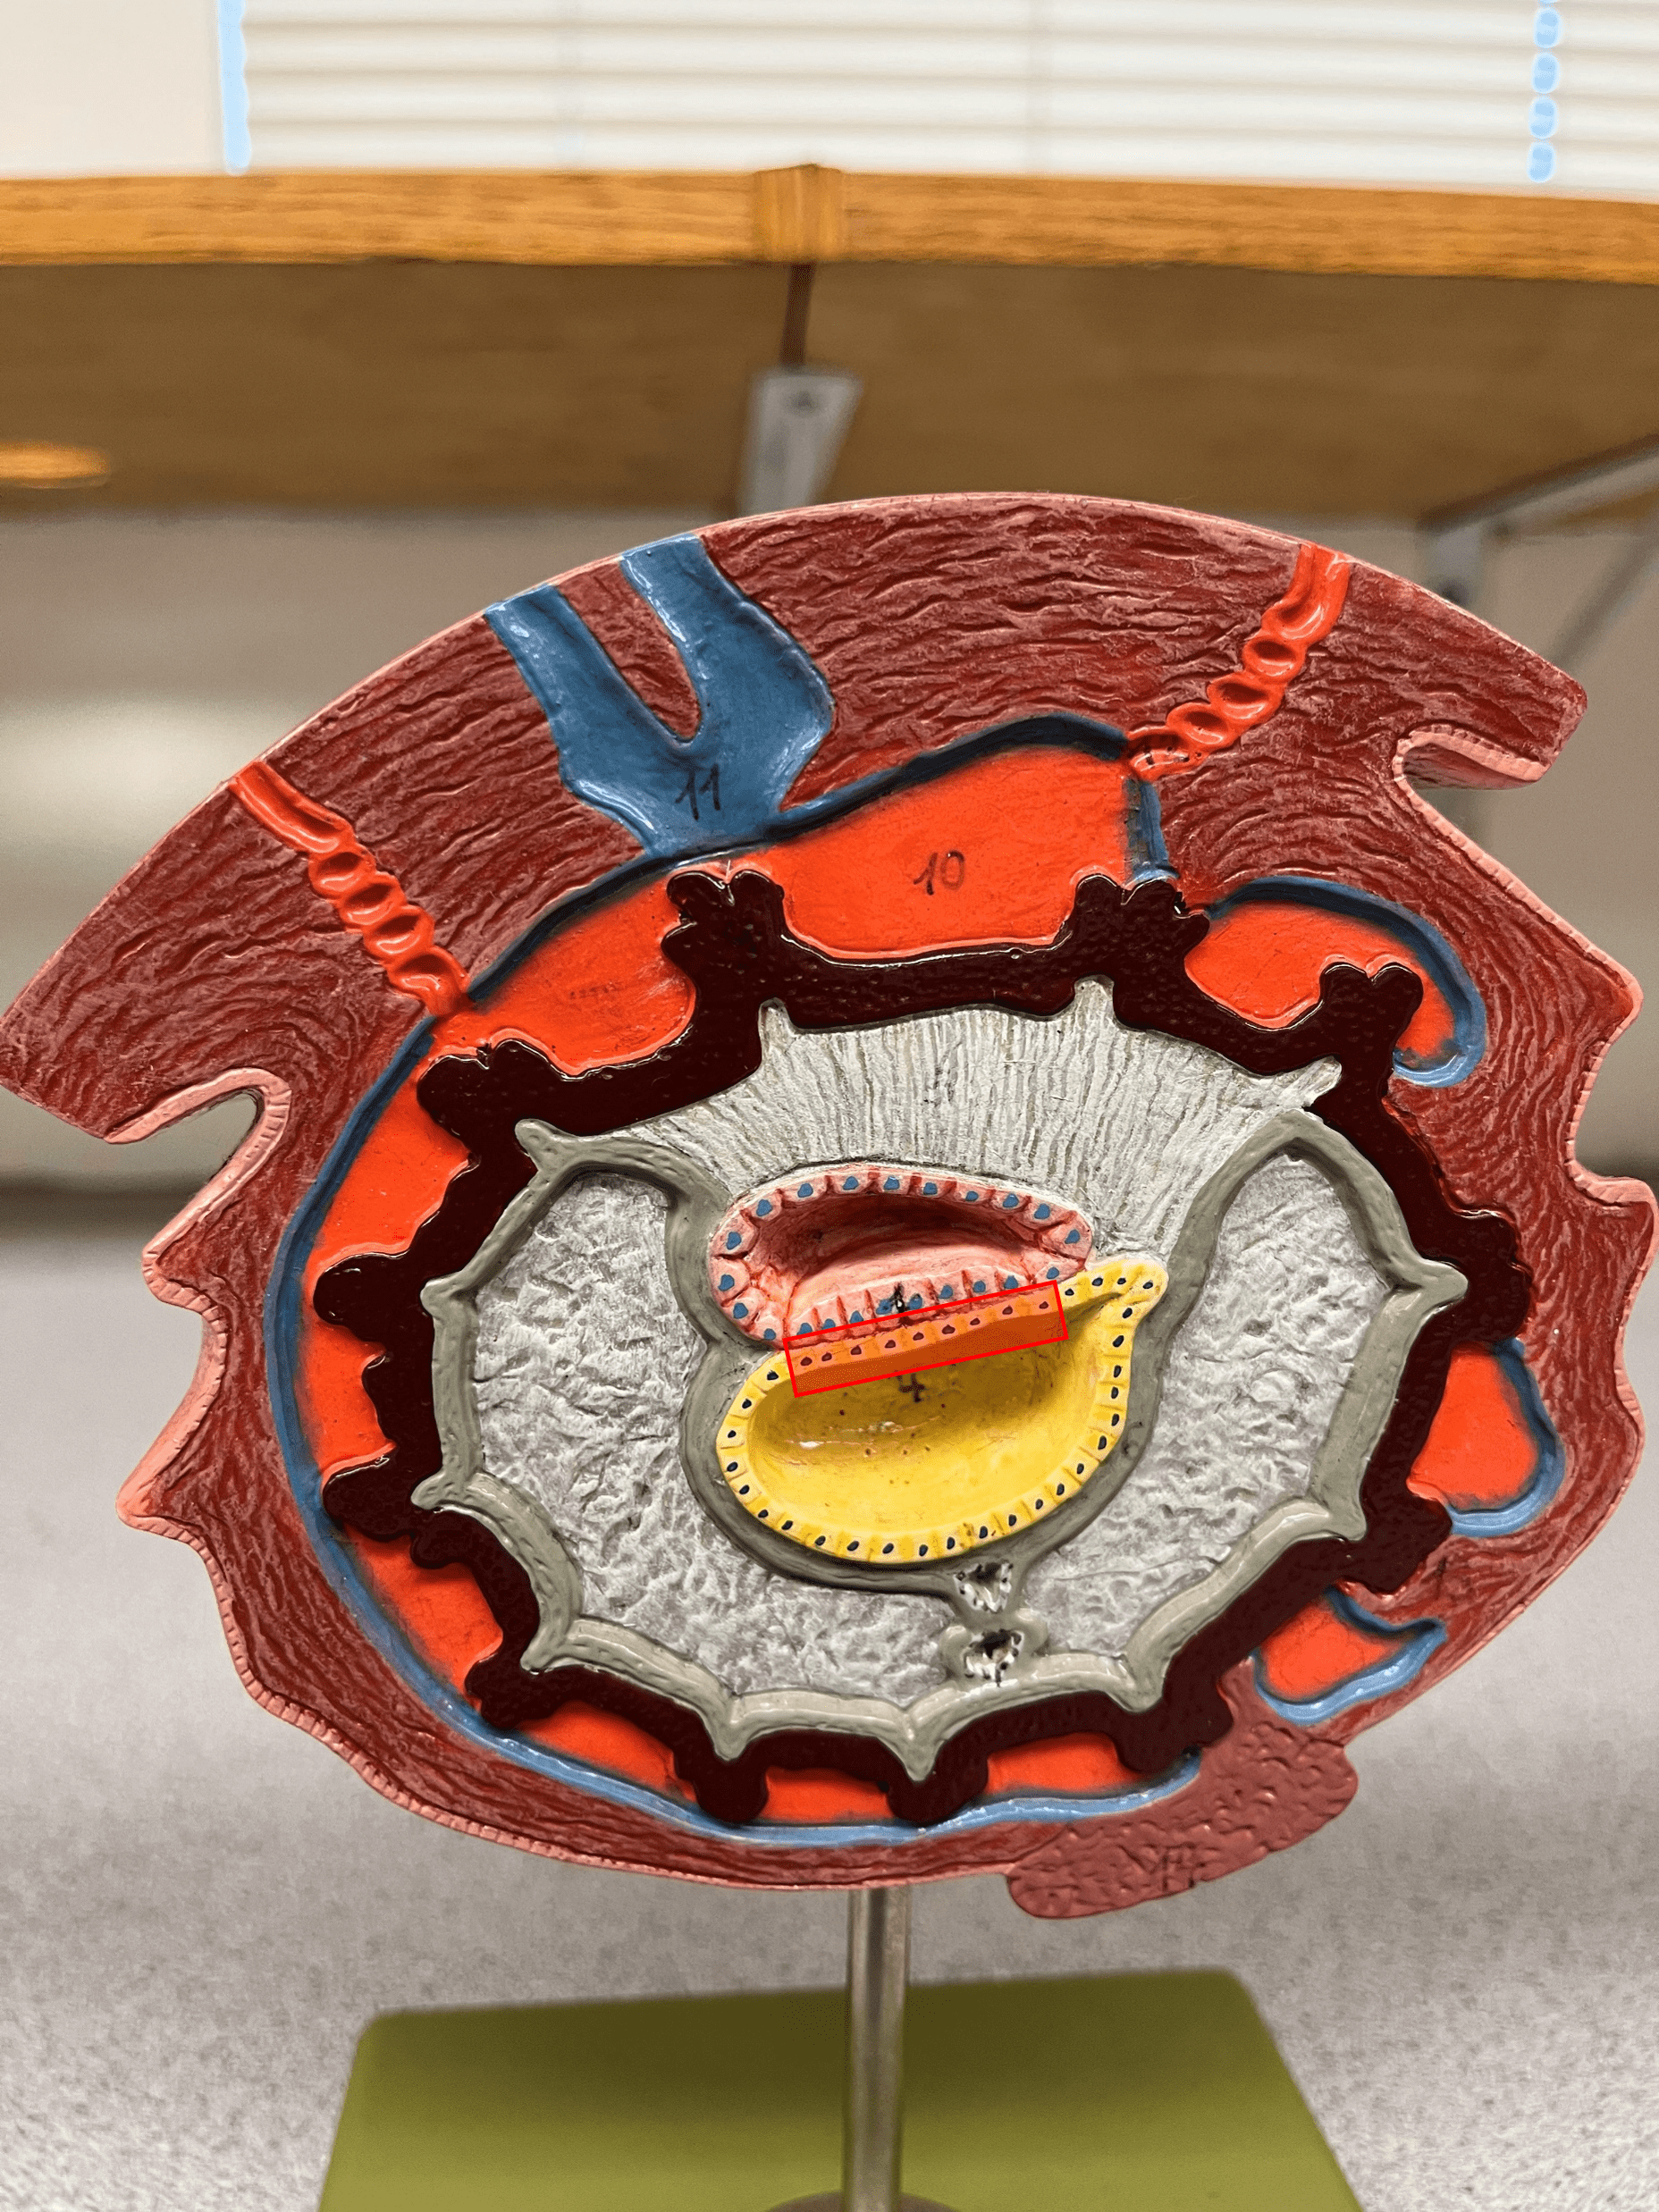

New cards

14

• Also known as a placental sinus.

New cards

20

21

22

• Becomes the fossa ovalis.

• Shortcuts blood from the pulmonary trunk to the aorta, bypassing the pulmonary circuit.